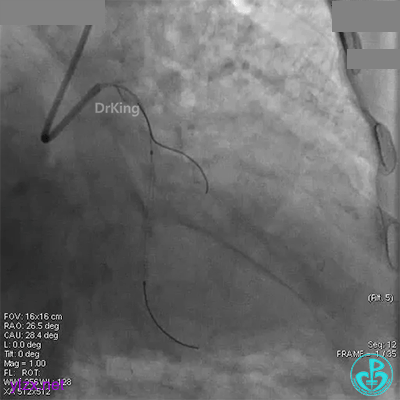

回旋支中段植入2.75×33mm支架后造影,前向血流中断,患者开始出现胸痛。

闭塞段植入2.75×33mm支架后前向血流中断,要排除无复流和支架两端夹层。